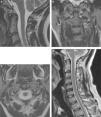

Las técnicas de imagen proporcionan una imagen anatómica excelente de la columna cervical. La elección de cada una de ellas dependerá del escenario clínico y de las alternativas terapéuticas. La radiografía simple sigue siendo fundamental, ya que permite valorar la alineación, las alteraciones óseas y el seguimiento tras el tratamiento. La mayor resolución de contraste de la resonancia magnética permite la valoración de las partes blandas, incluyendo los discos intervertebrales, los ligamentos, la médula ósea y la médula espinal. El papel de la tomografía computarizada en el estudio de la patología degenerativa ha cambiado en los últimos tiempos debido a la gran resolución espacial y su capacidad para visualizar el componente óseo.

Imaging techniques provide excellent anatomical images of the cervical spine. The choice to use one technique or another will depend on the clinical scenario and on the treatment options. Plain-film X-rays continue to be fundamental, because they make it possible to evaluate the alignment and bone changes; they are also useful for follow-up after treatment. The better contrast resolution provided by magnetic resonance imaging makes it possible to evaluate the soft tissues, including the intervertebral discs, ligaments, bone marrow, and spinal cord. The role of computed tomography in the study of degenerative disease has changed in recent years owing to its great spatial resolution and its capacity to depict osseous components.